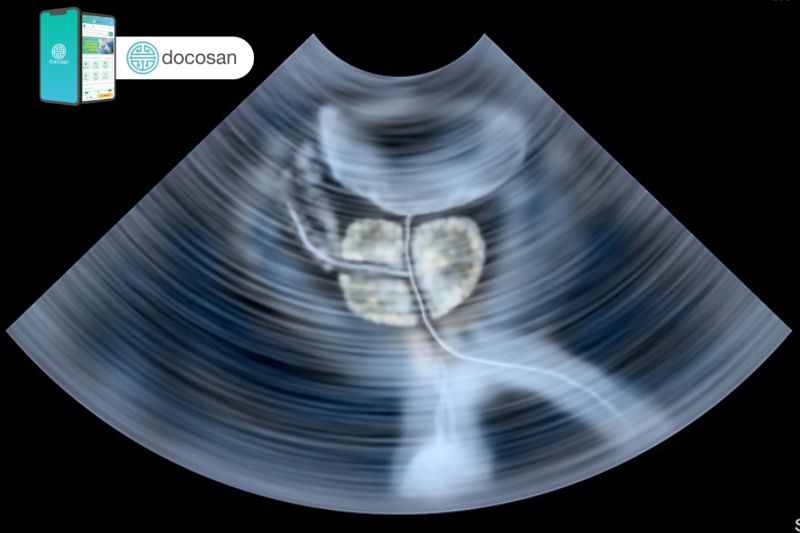

Hiện nay có nhiều phương pháp điều trị hiệu quả cho u phì đại tiền liệt tuyến và cần bác sĩ xem xét các triệu chứng, kích thước của tuyến tiền liệt và các vấn đề sức khỏe khác. Điều trị u phì đại tiền liệt tuyến bao gồm các liệu pháp nội khoa sử dụng thuốc, thay đổi lối sống và phẫu thuật ngoại khoa.

Hầu hết nam giới sẽ được tiếp tục tăng trưởng tiền liệt tuyến trong suốt cuộc đời và sự tăng trưởng này trực tiếp gây ra u phì đại tiền liệt tuyến. Nếu kích thước u đủ lớn và gây chèn ép sẽ gây ra các triệu chứng tiết niệu do gây tắc nghẽn đáng kể lưu lượng nước tiểu. Các bác sĩ nam khoa không chắc chắn chính xác nguyên nhân làm cho tiền liệt tuyến ngày càng to ra, có thể là do những biến đổi sự cân bằng của hormone sinh dục nam của người lớn tuổi.